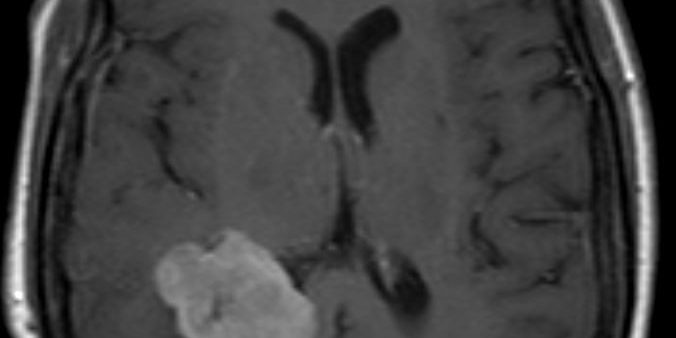

Ενδοκοιλιακό Μηνιγγίωμα Δεξιά